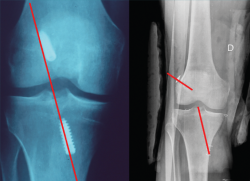

El estudio mediante TC, tanto en 2D como en las reconstrucciones actuales en 3D, va a ser de gran utilidad para poder identificar la posición de los túneles óseos tibial y femoral, la dirección de ambos y, finalmente, el grado de dilatación y la morfología de los mismos. Estos aspectos van a ser claves para poder planificar la cirugía de revisión en uno o dos tiempos (Figuras 3 y 4).

Figura 3. La tomografía computarizada en 2D mediante cortes axiales, coronales y sagitales permite conocer tanto la dirección como la morfología de los túneles previos, así como medir el grado de dilatación de los mismos para planificar la cirugía de revisión.

Figura 4. Actualmente, la reconstrucción en 3D de la tomografía computarizada permite comprender mejor la localización tridimensional de los túneles óseos.